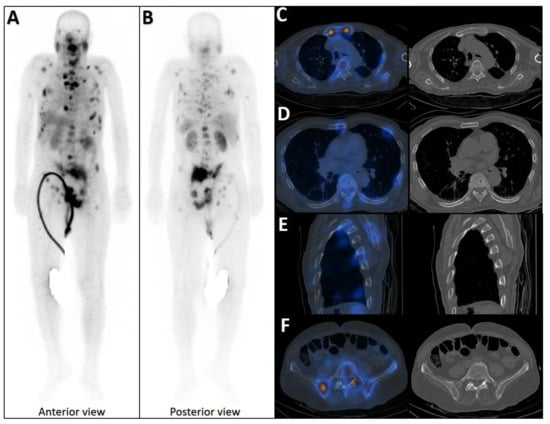

Figure 2.

Early phase of metastases without clear sclerotic changes in the bone. (A) 70-year-old man with elevated PSA was recently diagnosed with prostate adenocarcinoma (all cores positive with Gleason score 5 + 4) and referred for staging. The whole-body 99mTc-PSMA scan (A,B) and SPECT/CT showed multiple PSMA-avid skeletal metastases, most of which showing no/minimal density changes (C–F).

Figure 3.

False positive findings in bone scintigraphy due to rib fractures. A 78-year-old man with prostate adenocarcinoma (biopsy Gleason score 4 + 4, serum PSA = 56.8 ng/mL) was referred for staging. Whole-body bone scan revealed two consecutive focal osteoblastic activities in the lateral arc of the ribs on the right side (A,B). 99mTc-PSMA SPECT/CT (C) revealed increased tracer uptake in the prostate gland (D), multiple metastatic lymphadenopahies on the left side of pelvis and para-aortic regions (red arrow, (E)). Moreover, fractures in the right 6th and 7th ribs showed no PSMA avidity (white arrowheads, (F,G)).